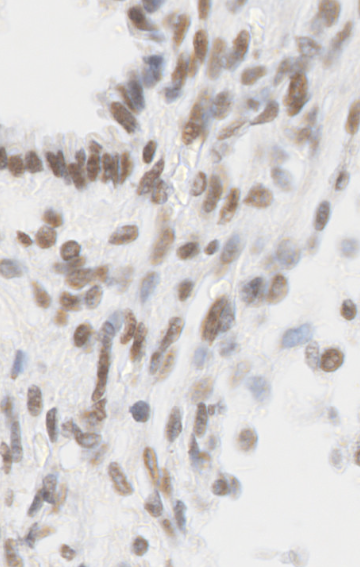

The data presented in this study have been acquired from digital images of immunohistochemistry stainings that were performed on archival tissue obtained from the neurobiobank of the Division of Neuropathology and Neurochemistry at the Medical University of Vienna. Stainings have been performed according to standard procedures (citep \@BBN(Guo et al., 2024; Schwaiger et al., 2023)). Figure 11 (a)-(c) shows a tumour biopsy of a gliosarcoma patient stained for the astrocyte marker GFAP (brown signal, cytoplasmic localization) and counterstained with Hematoxylin (blue signal, nuclear localization). Figure 3 (d)-(e) shows fetal cerebellar tissue stained for the epigenetic mark H3K27me3 (brown signal, nuclear localization) and counterstained with Hematoxylin (blue signal, nuclear localization). The stained sections have been digitalized on a NanoZoomer 2.0-HT digital slide scanner C9600 (Hamamatsu Photonics, Hamamatsu, Japan). The corresponding software NPD.Viewer2 was used to export the scanned images to tiff files. Here, we performed individual scans of a selected imaging area with different numbers of focus points. We chose either 1, 3 or 9 focus points while not changing the spatial settings for the selected field of interest. The image with 9 focus points, allowing the highest resolution, serves as the reference image.

Refer to caption

(d) Reference

(e) (22.9, 0.81, 0.11)

(f) (27.0, 0.87, 0.22)

Figure 11: Data acquired with a slide scanner and 9 (a)(d), 3 (b)(e) and 1 (c)(f) focus points. The image with 999 focus points serves as a reference here. PSNR and SSIM misjudge the tiny spatial misalignment and therefore favor the blurry images with 1 focus point. LPIPS is able to ignore these spatial misalignments.

FR-IQA mismatches

Although the spatial settings for the selected scan area of interest were not changed during the experiment, the physical performance of the scanner showed slight spatial deviations of the selected area between individual scans and thus does not allow for high spatial accuracy during re-scanning processes. PSNR and SSIM fail to correctly assess the images in Figure 11 as they are very sensitive to that kind of misalignments. Whereas clearly the scan with 3 focus points corresponds much better to the reference as the blurred scan with 1 focus point, see (b) and (e) versus (c) and (f), both measures incorrectly judge the blurred scan as better. This wrong judgement due to a tiny spatial change is very problematic in the respective framework, as it is impossible to guarantee completely exact spatial alignment, even if no other settings had been changed during the scanning process. LPIPS is able to correctly judge the rank of quality here.